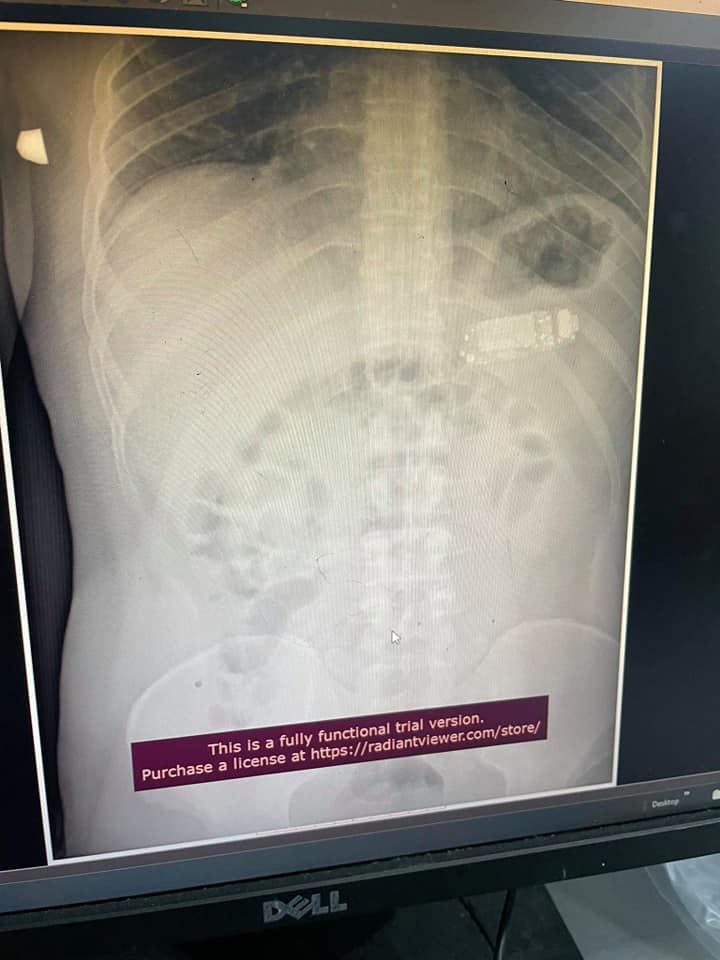

Мужчине сделали рентген и на снимке действительно обнаружили мобильный телефон с кнопками.

Хирургам пришлось провести сложную операцию и разделить телефон на три части с помощью эндоскопии. Посторонний предмет был слишком большим, чтобы желудок мог его переварить. Тем более, пациент был в опасности – аккумуляторная кислота могла вытечь и спровоцировать сильное отравление.